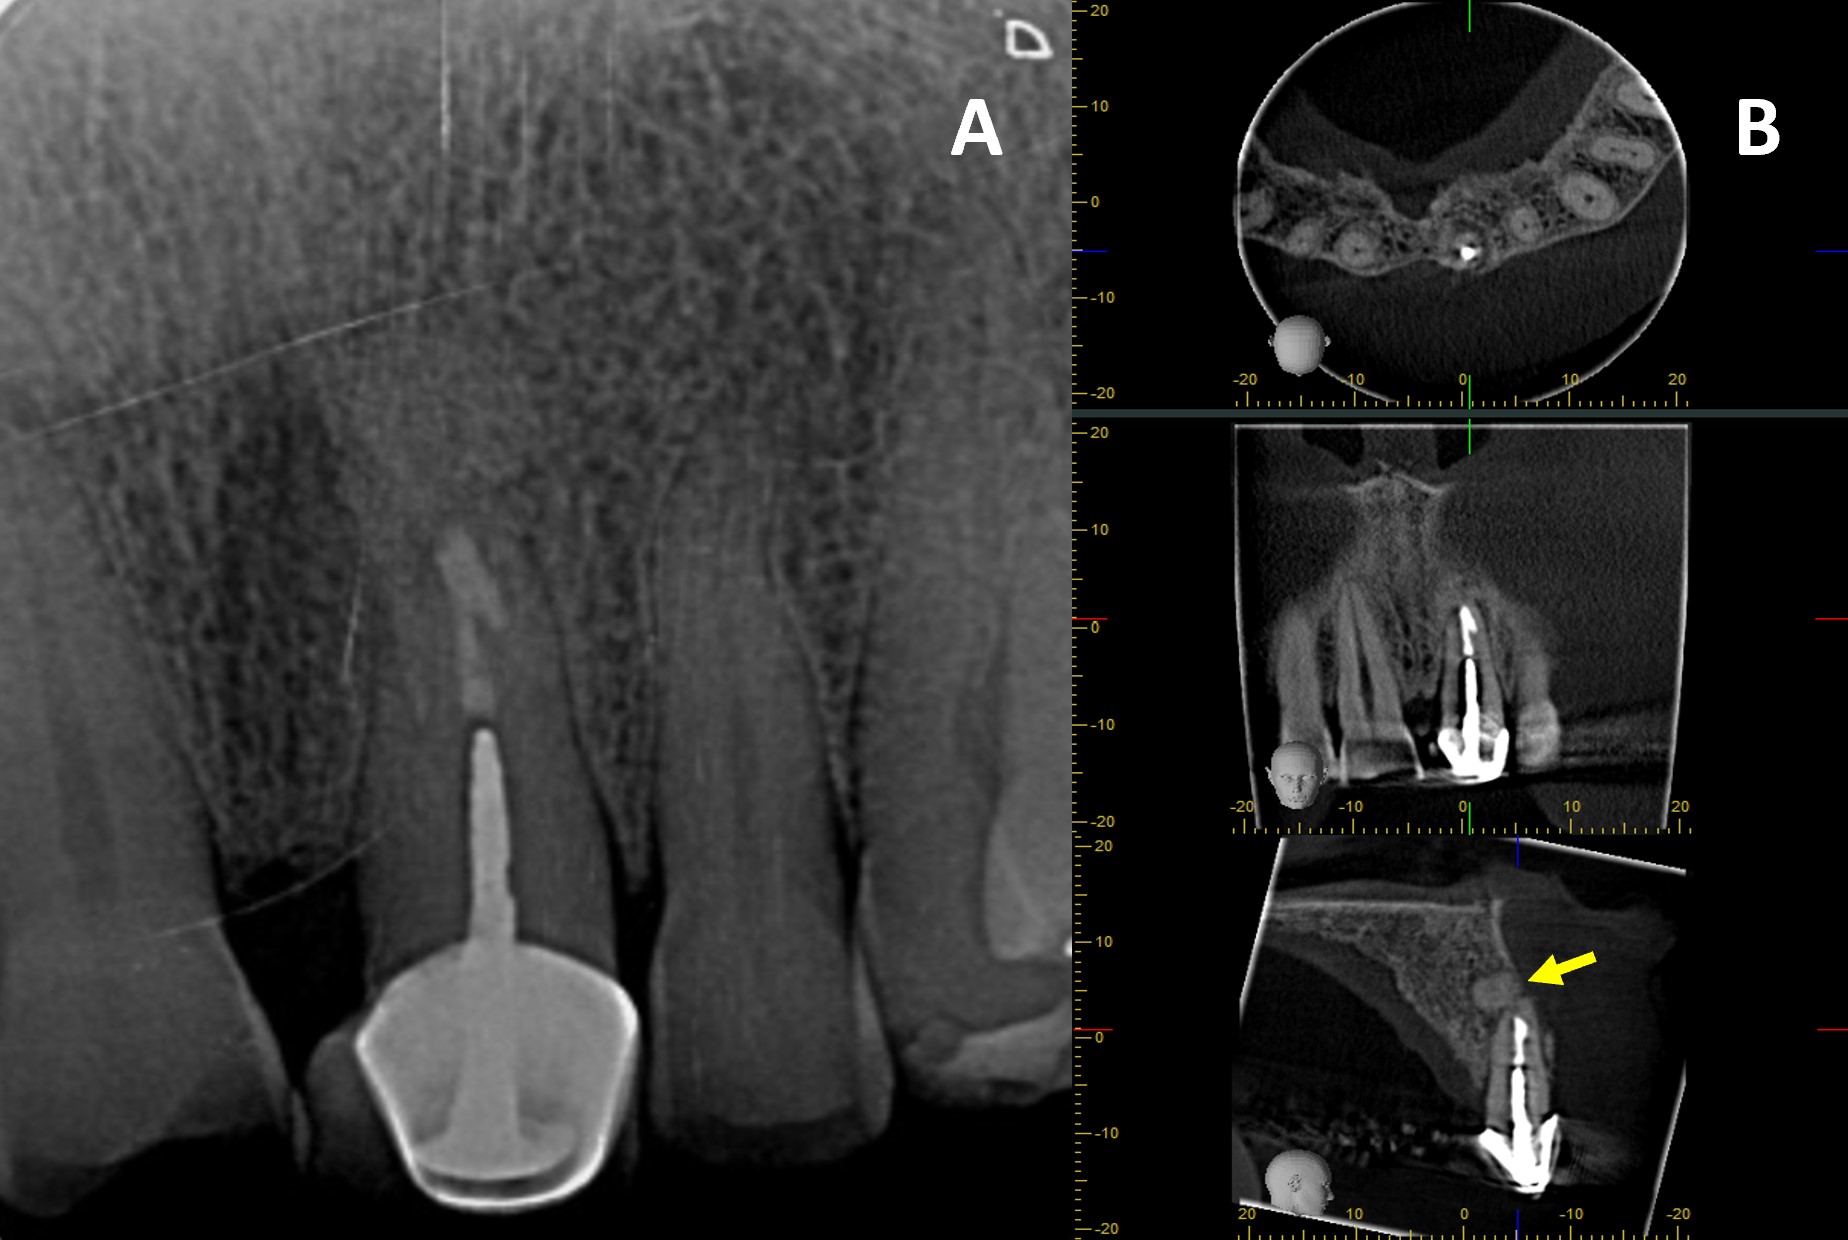

Finally, guided tissue regeneration was carried out using [1g] Quirubone bone graft with particle size [0.25-0.5 mm] (Cellstech, Itagüí, Colombia) and Quirumatriz membrane [15 x 20 mm] (Cellstech, Itagüí, Colombia) (Fig 2-M and 2-N). The flap was repositioned and sutured with resorbable Vicryl 5/0 (Vicryl Plus, Ethicon, India) (Fig 2-O). Postoperative care included amoxicillin [875mg/12h/5days], meloxicam [7.5mg/12h/3days], and mouth rinses with chlorhexidine [0.2%] (Clorhexol, Farpaq, Cali, Colombia) 10 ml-rinse for 60 s twice-a-day (every 12 h) for 7 days. Radiographic and tomographic assessment at eight months demonstrated ongoing healing of the affected periapical tissues. Furthermore, it was observed that the ultrasonic retropreparation did not follow the original trajectory of the root canal, as a slight deviation towards the distal wall was noted. In addition, the retrograde obturation material remained well positioned throughout the follow-up period, thereby supporting the favourable progression of periapical tissue repair (Fig 3 A-B).

CBCT has been recommended for the diagnosis, planning and follow-up in endodontics, due to its three-dimensional imaging, which overcomes the limitations of traditional periapical radiograph (PR) [10, 11]. In this case, CBCT identified a periapical lesion that was not visible on PR and enabled more precise surgical planning. Furthermore, the tomographic follow-up findings suggested ongoing periapical healing. Compared to PR, it may have been mistakenly considered a complete healing, which supports the use of CBCT for longer-term follow-up of this case.

Follow-up PR and CBCT confirmed the presence of retrofilling material. Bio-C Repair, a bioceramic cement containing tricalcium silicate, dicalcium silicate, tricalcium aluminate, calcium oxide, silicon oxide, zirconium oxide, polyethylene glycol, and iron oxide, was used. Its bioactivity encourages reparative cell growth and supports periapical healing [16]. Bio-C Repair is highly biocompatible and forms hydroxyapatite when in contact with tissue fluids, promoting osteoinduction and osteoconduction, and facilitating bone regeneration and repair of periapical tissues after endodontic microsurgery. Its ready-to-use presentation and expansion on setting improve adaptation and chemical sealing to dentine, reducing leakage and reinfection risk [16, 17]. Although a slight deviation of retropreparation was observed, this variation is not considered clinically significant as it did not compromise the adaptation or sealing ability of the retrofilling material, nor the biological processes essential for periapical healing [5].